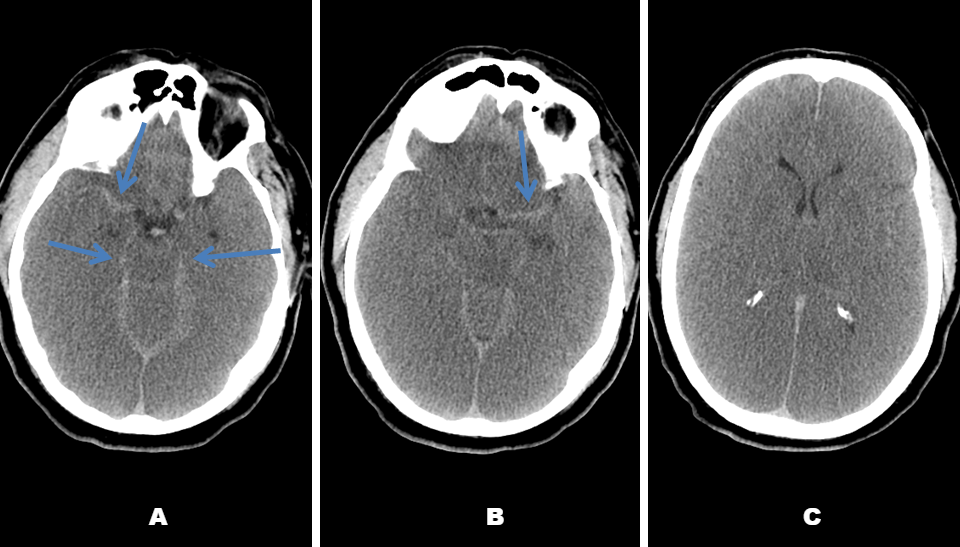

Pseudosubarachnoid Haemorrhage - a case discussion